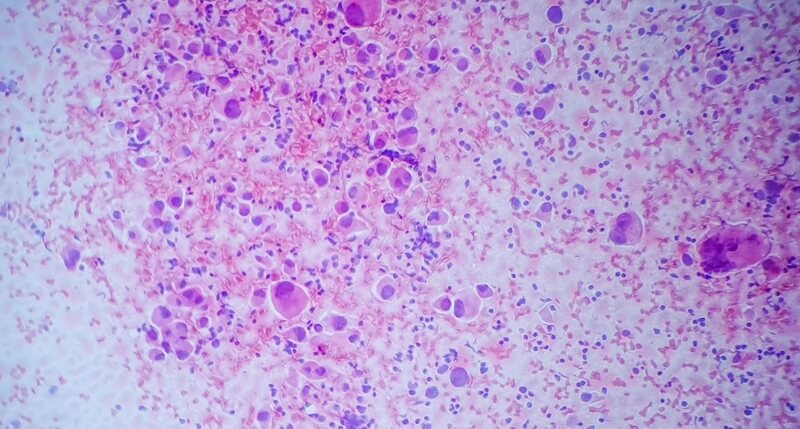

Adenocarcinomas

A maior parte dos casos de câncer colorretal são do tipo adenocarcinoma. Os adenocarcinomas são tumores de natureza maligna que se derivam de células glandulares epiteliais secretoras.

Quando estamos falando de câncer colorretal, os adenocarcinomas são o tipo mais comum, mas não o mais agressivo – sobretudo se for descoberto nas etapas iniciais do seu progresso.

No entanto, quando não tratados, os adenocarcinomas têm por característica uma maior facilidade para atingir outros órgãos do corpo, fazendo com que o câncer possa se tornar uma doença cada vez mais difícil de controlar.